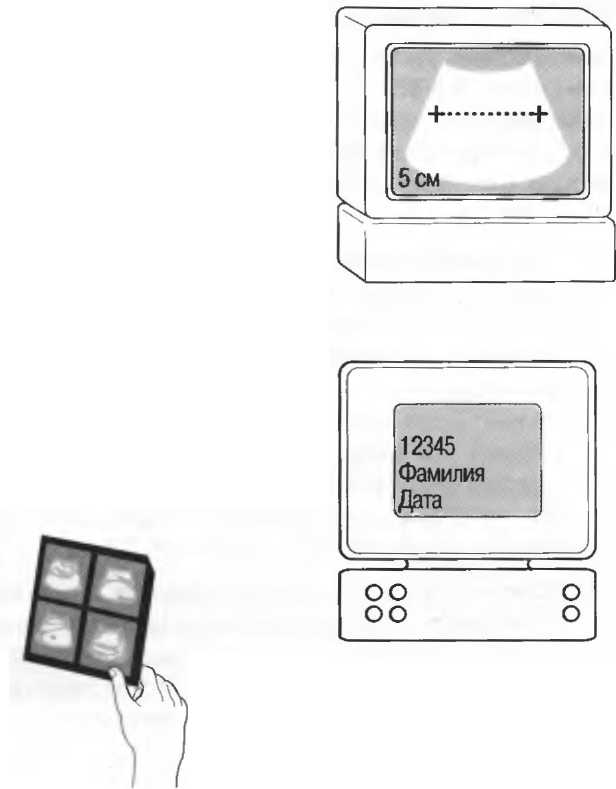

Функции измерения, которое должно производиться электронным способом и обычно производится помещением маленьких маркеров — точек по обе стороны измеряемого расстояния. Значение расстояния автоматически высвечивается на экране в сантиметрах или миллиметрах. В акушерстве используются специальные биометрические таблицы.

Регистрация изображения

Необходимо, чтобы была возможность добавлять к изображению идентификационные и другие данные пациента: крайне желательно, чтобы наиболее важные эхограммы фиксировались в истории болезни пациента. Есть несколько способов, различных по стоимости и эффективности, сделать это.